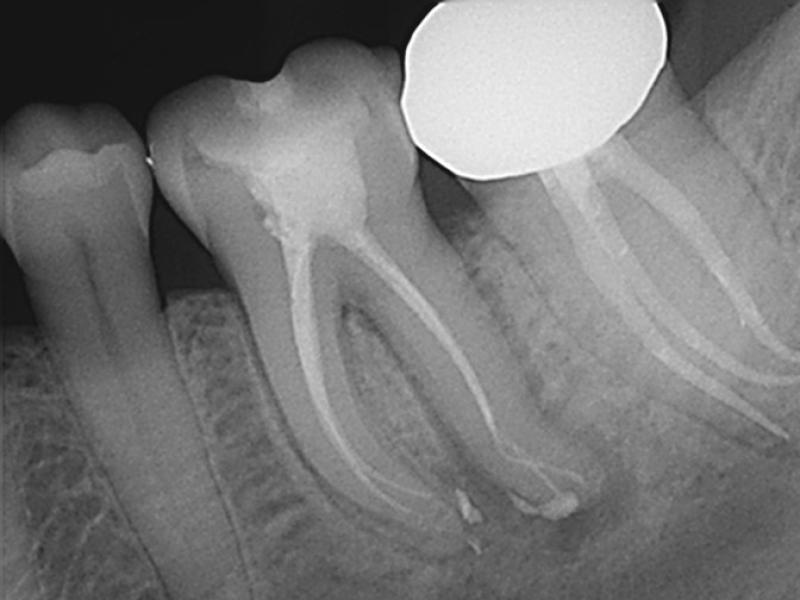

Post-Op